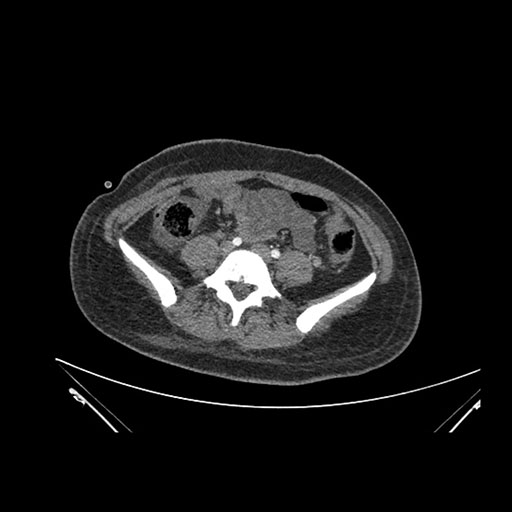

Imaging Analysis

Look through the patient's CT scan to identify any areas of concern for the necessary procedure.

Axial Venous